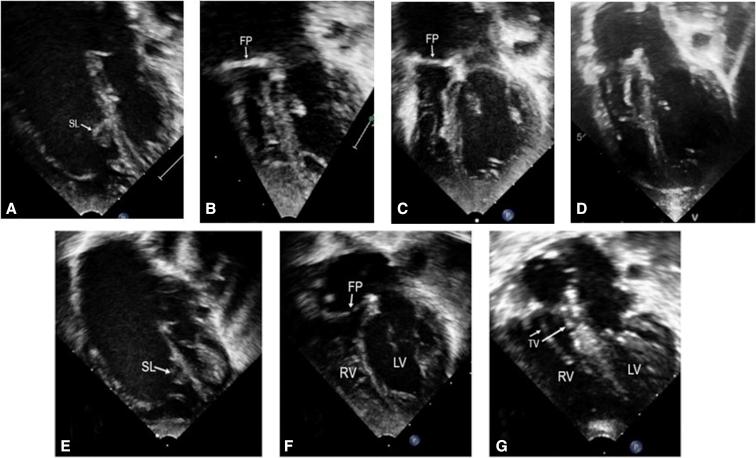

The Da Silva cone operation after the Starnes procedure for Ebstein's anomaly: New surgical strategy and initial results.

JTCVS Tech. 2020 May 17;3:281-283. doi: 10.1016/j.xjtc.2020.05.011. eCollection 2020 Sep.

https://cdn.ncbi.nlm.nih.gov/pmc/blobs/f754/8302946/c3f2a06919a7/gr2.jpg

https://cdn.ncbi.nlm.nih.gov/pmc/blobs/f754/8302946/188979fb8303/gr1.jpg